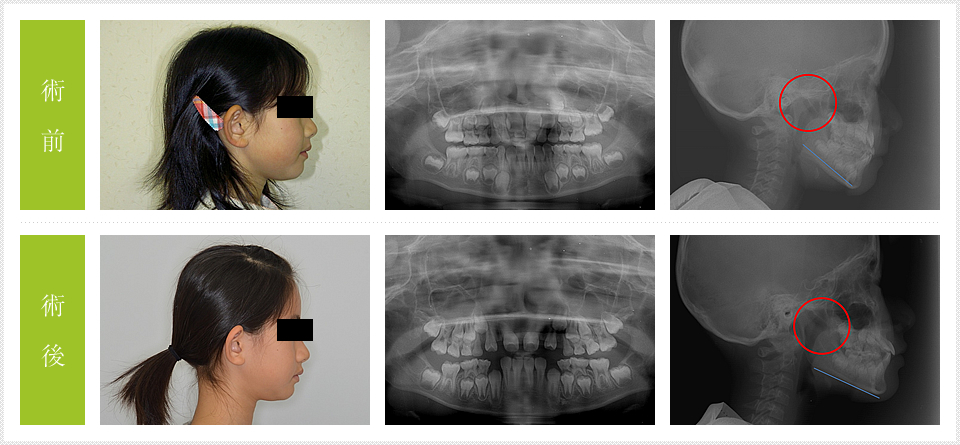

頭のレントゲンを見ると術前は、鼻の気道が狭く、舌骨が下がっているのがわかります。舌の位置は舌骨が頚椎のどの高さにあるかで見ます。最初は4番目付近ですが、術後は3番ぐらいまで上がっています。これは大変な変化で当然、鼻の気道も広がっています。(赤○印)

このことは上下の顎を側方に広げ、上顎の前歯を上前方に上げて舌が引き上げられた結果です。

ランパはこの上顎骨を上げるのと前歯を上前方に位置づけるのを一気に行う装置です。